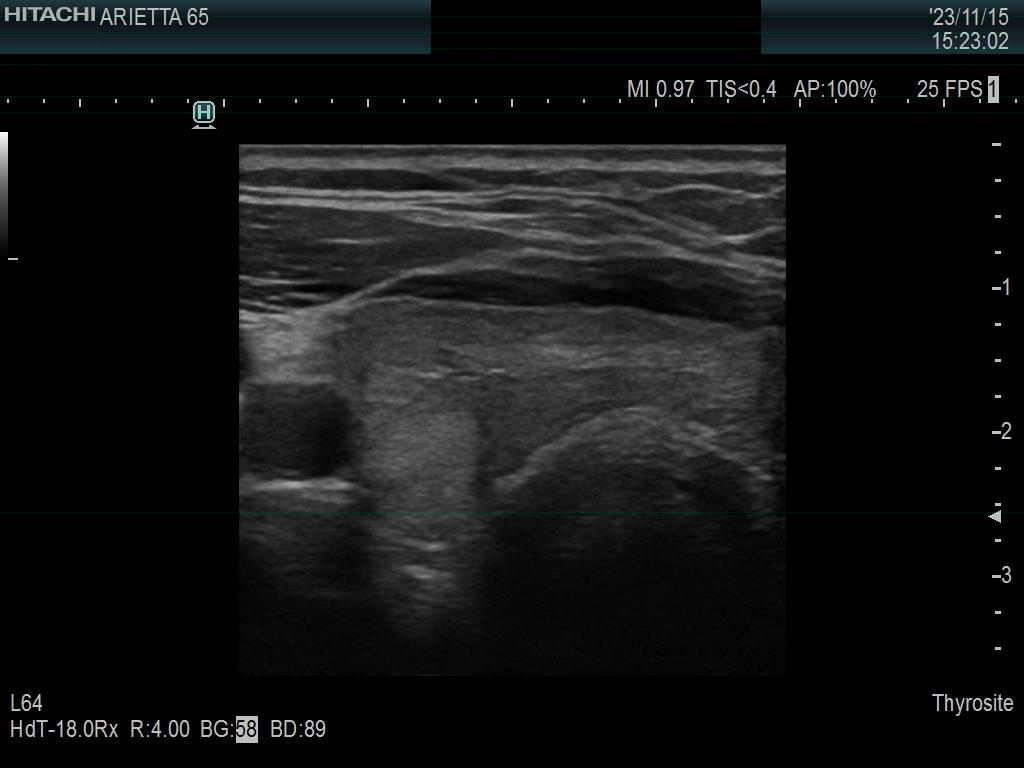

Ultrasonography. The thyroid was minimally hypoechoic. The echogenicity of the dorsal part of the left lobe where the nodule was previously described did not differ from other parts of the thyroid. There was a connective tissue running ventral to this part of the lobe and hypoechoic areas were found upper and dorsal to this. Neither halo nor perinodular blood flow was present.

The area in question did not correspond to a pathological nodule. It seemed to be circumscribed because of the presence of connective tissue and thyroid vessels.

A follicular tumor must have a capsule which ultrasound sign, either a complete halo and/or perinodular blood flow are present in more than 95% of cases. Both features were absent in this case.